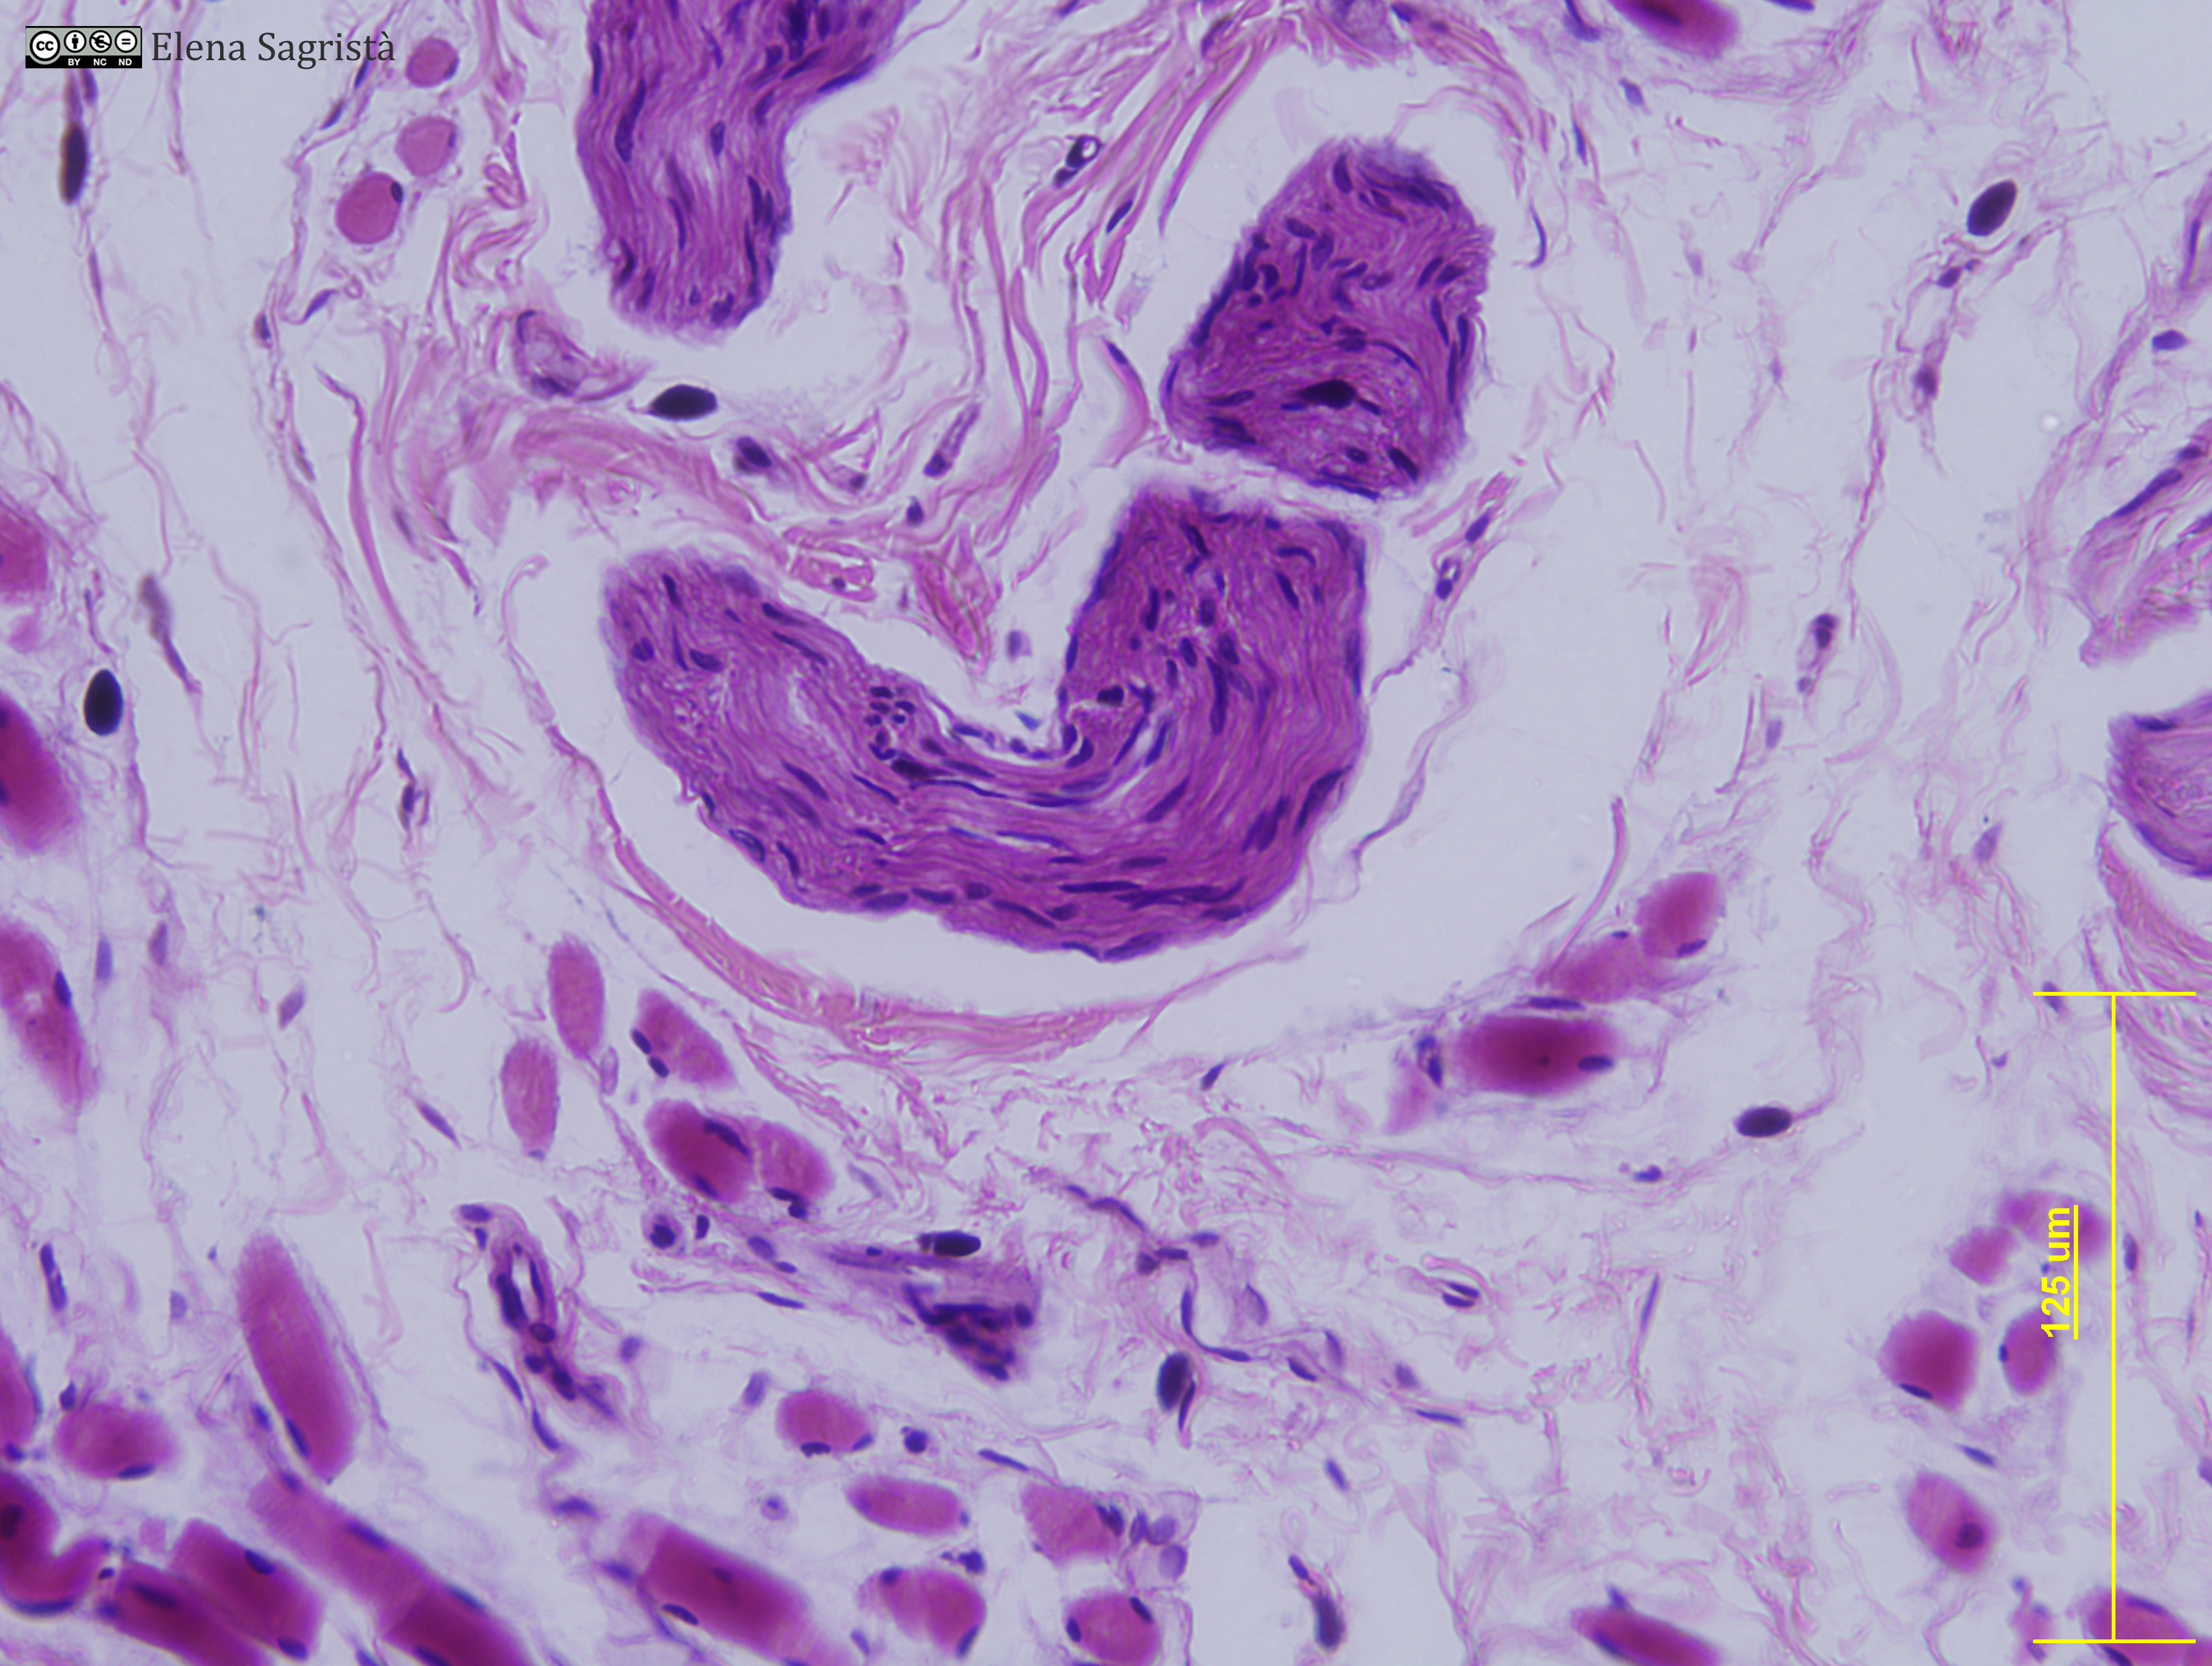

Histologia imatges: 09 Teixit nerviós perifèric

Imatges de preparacions histològiques de Teixit nerviós perifèric. Microscopia òptica.